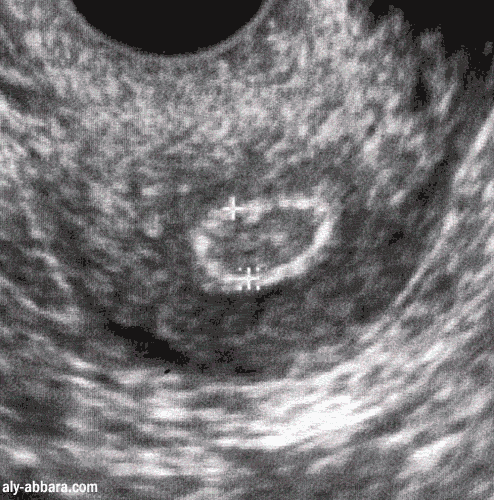

Fibrome utérin (myome) sous muqueux (ou endocavitaire)

Image animée comparant l'aspect échographique et hystérosalpingographique du même fibrome.

Ce myome est à l'origine de ménorragie importante entraînant une anémie chronique